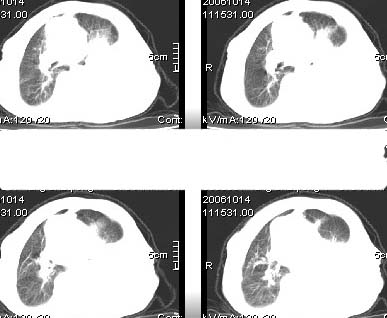

标题: CT4907:[原创]胸部平扫,请讨论!谢谢!!

左侧大量胸腔积液伴左下肺不张,左侧支气管狭窄,左舌段有膨胀感,中央型肺癌待排,心包有少量液体。肝顶部低密度影,需进一步检查

好象在右肝上看到一个低密度的东西?

左侧大量胸腔积液,左下叶受压不张,纵隔向右侧轻移位,虽未见明显骨质破坏,但临床有刺激性咳嗽、胸疼等都支持非善类病变,应穿刺抽液细胞学检查,考虑右肺癌并胸膜转移。肝顶部似有低密度影,可进一步检查,排除转移灶。

患者以抽胸水到上级医院作细胞学检查,肝右顶部的确是{患者以作b超:囊性低密度区,考虑囊肿?}病灶。我的初步意见是考虑是左侧中央型肺癌。

大量胸水建议抽水后复查 ,压迫性肺不张,肝右叶低密区结合患者临床症状多考虑左肺恶性病变.

1、高度怀疑:左肺中央型肺癌伴肺不张、胸水;

2、肝上病灶暂考虑囊肿。

左侧胸腔积液,左下肺压迫性不张,建议抽胸水细胞学检查或增强.肝右叶低密度影,建议增强.心包内未见积液征.